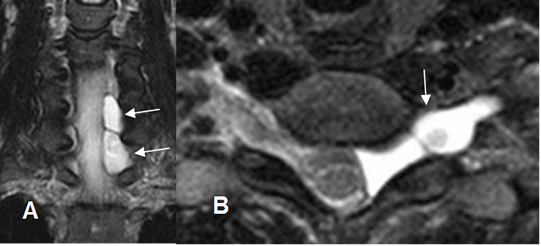

Fig 229. Quiste no meníngeo.

A: RM axial y B: RM sagital en T2. Hipertrofia de articulaciones intervertebrales, con formación de lesión quística yuxta-articular a nivel paramediano derecho, que comprime el saco dural.